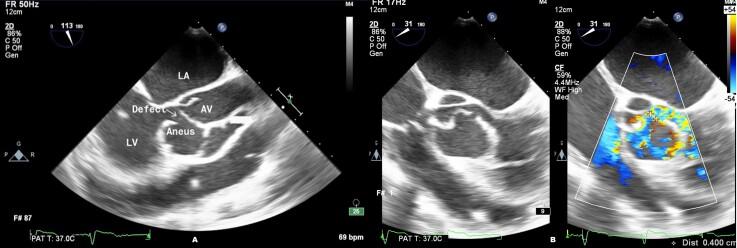

Aortic cuspal aneurysm is a rare clinical entity and often occurs as a complication of infective endocarditis. We report a case of a 30-year-old male with no prior comorbid conditions who presented with fever, acute onset shortness of breath, and chest pain along with multiple episodes of syncope. Electrocardiogram revealed complete heart block while two-dimensional echocardiogram was suggestive of perforated aortic cuspal aneurysm with aortic regurgitation. Blood cultures were positive for . The patient was initiated on broad spectrum antibiotics, temporary pacemaker implantation, and subsequently underwent aortic valve replacement followed by permanent pacemaker implantation after 6 weeks. A diagnosis of perforated aortic cuspal aneurysm subsequent to infective endocarditis was made. This was based on clinical presentation, echocardiographic evaluation, blood cultures, and surgical as well as histopathological findings.

主动脉瓣叶动脉瘤是一种罕见的临床病症,常作为感染性心内膜炎的并发症出现。我们报告一例30岁男性病例,该患者既往无合并症,表现为发热、急性起病的气短、胸痛以及多次晕厥发作。心电图显示完全性心脏传导阻滞,而二维超声心动图提示主动脉瓣叶动脉瘤穿孔伴主动脉瓣反流。血培养结果为……阳性。患者开始接受广谱抗生素治疗、临时起搏器植入,随后接受主动脉瓣置换术,6周后植入永久起搏器。诊断为感染性心内膜炎继发的主动脉瓣叶动脉瘤穿孔。这一诊断基于临床表现、超声心动图评估、血培养以及手术和组织病理学检查结果。